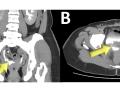

Diagnóstico por imagem em ginecologia - Quinto ano medicina